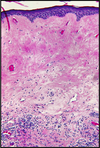

Disease

Microscopic findings

Lichen Sclerosus

marked thinning of the epidermis

degeneration of the basal cells

hyperkeratosis

sclerotic changes of the superficial dermis

bandlike lymphocytic infiltrate in the underlying dermis